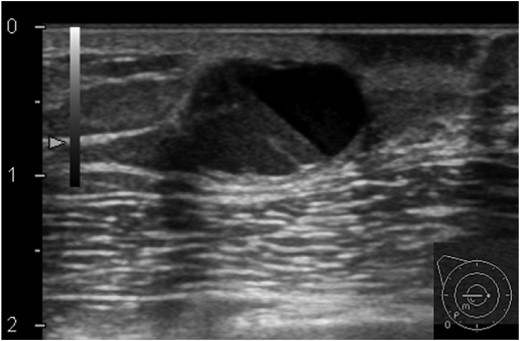

A 56-year-old Japanese man presented with eczema and redness of the right nipple (Fig. 1) and an 11 mm lump located in the right sub-areolar area. He had no notable familial history, and had no medical history except surgery for a cerebral hemorrhage 2 weeks previously. Ultrasound revealed a cystic mass below the right areola (Fig. 2), but no obvious invasive tumor. Skin biopsy of the nipple eczema revealed Paget's cells in the epidermis and possible invasive foci infiltrating the underlying dermis. Computed tomography revealed only a cystic mass in the right breast and no distant metastasis.

Ultrasonography of the right breast at first presentation. A cystic mass, 13 mm, with the appearance of rippling water can be seen below the right areola.